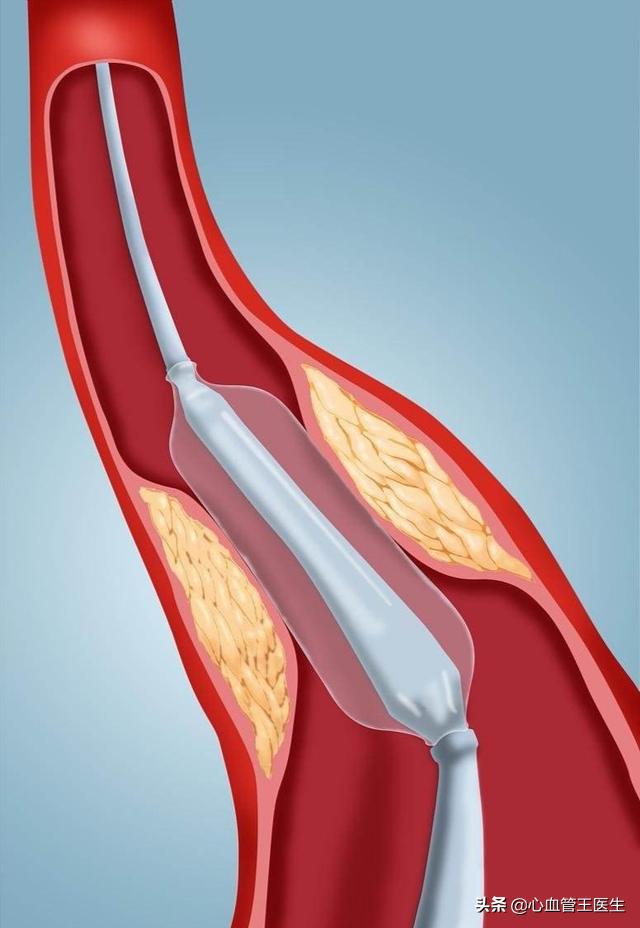

私たちは皆、多かれ少なかれ知っているはずだ。冠状動脈性心臓病とは、主に心臓の冠状動脈が狭くなる病気である。心臓に血液を供給する血管の狭窄は、心筋虚血や心筋壊死を引き起こす可能性があり、この狭窄を解消して冠動脈への血液供給を回復させるために、治療法のひとつは次のようなものである。何か支えとなるものを持っていく。それこそが、今、私たちが話しているブラケットなのだ。

ステップ3:軌道を確立する。最初のガイドワイヤーは冠動脈より太いので、この時は細いガイドワイヤーを選んで冠動脈病変の遠位部を通過させ、まずバルーンで拡張しなければならない。

ステップ4:ステントを留置する。バルーンの拡張が完了したら、このガイドワイヤーに従ってステントを留置する。